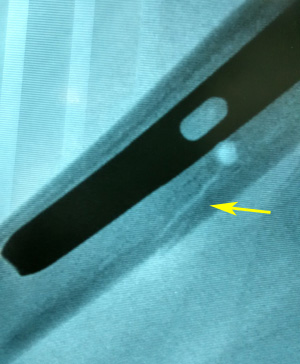

There can be hitches while reaming over guide wire for hip screw, as guide wire may bend slightly as it reaches the hard subchondral bone. Drilling over bent guide wire may result in its breakage. We had 3 such complications. We recommend partial drilling over guide wire just proximal to bend, followed by pulling of guide wire up to the level of its bend, then drilling of hard subchondral bone by drill bit itself under C - arm guidance to prevent guide wire breakage. The guide wire is then reinserted after the removal of reamer for screw insertion. One should also avoid using previously damaged guide wires. Sometimes there is mismatch between the jig and the nail leading to difficulty in negotiating the drill for the hip screws due to some manufacture or implant assembly related problems. We had 4 such problems, three for lag screw and one for derotation screw. Prior to nail insertion, one should check the jig nail assembly for its alignment. Drilling with smaller sized reamer and proceeding with regular reamer will also help. One should also check the jig whether it is loosened or not. Sometimes manipulation and hammering may result in loosening of jig and subsequent mismatch. Sometimes distal locking may also be troublesome. In one of our case distal locking bolt missed the nail while in another hammering the Steinmann pin to make entry portal for locking bolt, resulted in iatrogenic fracture (Figure 4a & b). Patient was put on long leg slab, which resulted in healing of the iatrogenic fracture. One should always do locking with drill bits and should avoid doing with Steinmann pin and hammer, which may shatter the cortex as was seen in our patient.

Figure 4a Image showing the iatrogenic fracture of the femur at locking bolt site, as a result of hammering the Steinmann pin to make entry portal for locking bolt (arrow).